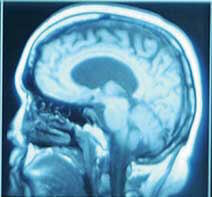

Curcumine et cerveau

L'organisme humain possède certains gènes qui régulent l'activité antioxydante. Un de ces gènes, héméoxygénase-1 (HO-1), est supposé défendre les cellules du cerveau exposées aux attaques radicalaires. Dans de précédentes études, la curcumine, dans des cellules de rat, encourageait fortement l'expression et l'activité de HO-1, indiquant que ce composé du safran pouvait aider à enrayer les effets de l'oxydation. |

Dans le but de confirmer ces données et de déterminer si la curcumine pouvait avoir des effets similaires sur des cellules du cerveau, des chercheurs ont examiné les effets neuroprotecteurs de la curcumine et sa capacité à provoquer la réponse de HO-1 dans des cultures de neurones de l'hippocampe. Le traitement par la curcumine a eu pour résultat une augmentation de l'expression de HO-1 ainsi qu'une expression plus importante des enzymes antioxydantes. La pré-incubation des cellules dans la curcumine augmentait la résistance des cellules aux lésions oxydatives. |

Selon les chercheurs, cette étude indique que la curcumine pourrait être utilisée dans un but thérapeutique comme un puissant inducteur de HO-1 qui pourrait protéger les cellules du cerveau contre les lésions oxydatives. Les chercheurs réclament des études supplémentaires in vitro et in vivo pour déterminer si la curcumine peut prévenir les maladies neurodégénératives. |